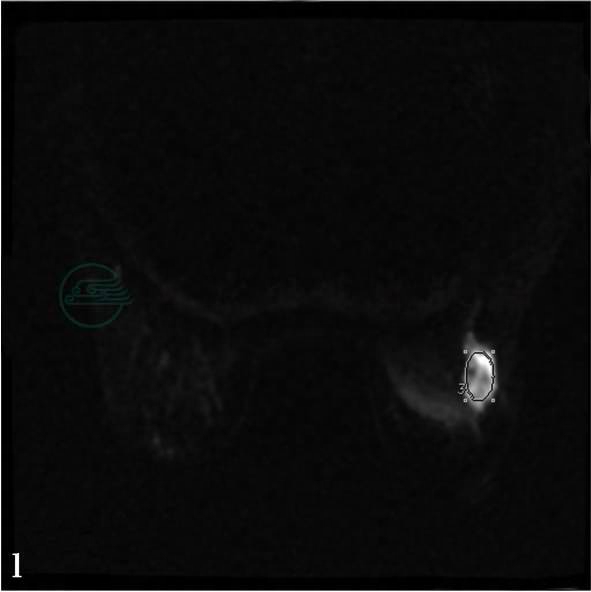

MRI平扫及增强扫描。

图4 图4f~i,分别为MRI动态增强前及增强后1min、2min、8min。图4j,病变时间-信号强度曲线图。图4k,MIP图。图4l,右乳病变DWI图。MRI显示右乳外上方不规则肿物,大小2.0cm× 3.0cm,边缘细小分叶及毛刺,动态增强后肿物呈明显强化(图g、h、i箭头所示)。图4j,时间-信号强度曲线呈“快进快出”流出型。图4k,右腋下相当于胸外侧动脉周围可见多发淋巴结,其中最大者为1.8cm×2.2cm(箭头所示)